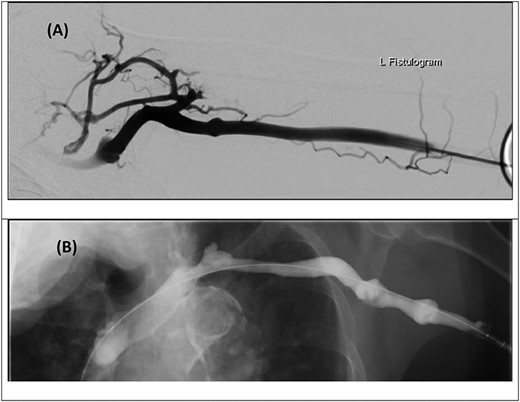

Thrombectomy was performed using the JETi Thrombectomy System™ (Walk Vascular LLC, CA, USA) of the left subclavian vein thrombus within 24 hours of symptom onset. Post-thrombectomy venogram demonstrated good restoration of flow; however, a short proximal subclavian vein stenosis was identified and treated with 8 × 40 mm balloon venoplasty. A good venographic result was seen on completion (Fig. 2).

Digital subtraction venogram images prior to thrombectomy demonstrating occlusive thrombus at the proximal left subclavian vein/axillary vein confluence with numerous collateral vessels within the shoulder and axilla (A and B). (C) Post-thrombectomy venogram demonstrating improved flow with no further collateral vessels noted.